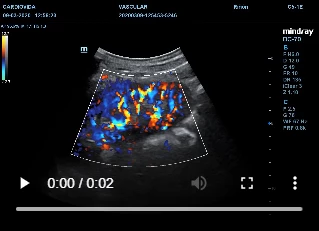

Doppler de vasos renales en Medellín

¿En qué consiste el doppler de vasos renales ?

Este procedimiento permite ver internamente como están los riñones y la circulación.

Se ordena principalmente en pacientes con hipertensión arterial para descartar estenosis renal.